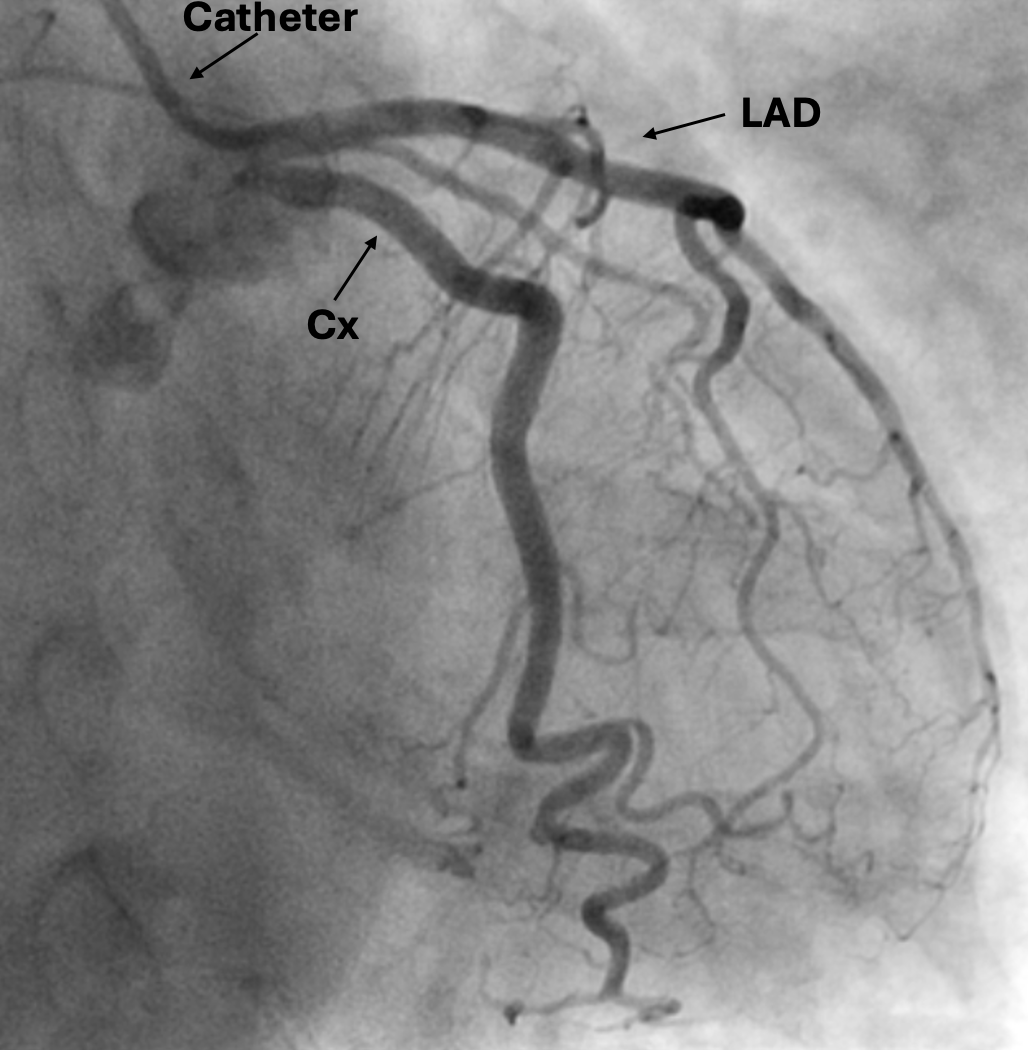

Coronary angio:

RCA: right coronary artery

PLV: posterior left ventricular artery

PDA: posterior descending artery

LAD: left anterior descending artery

Cx: circumflex artery